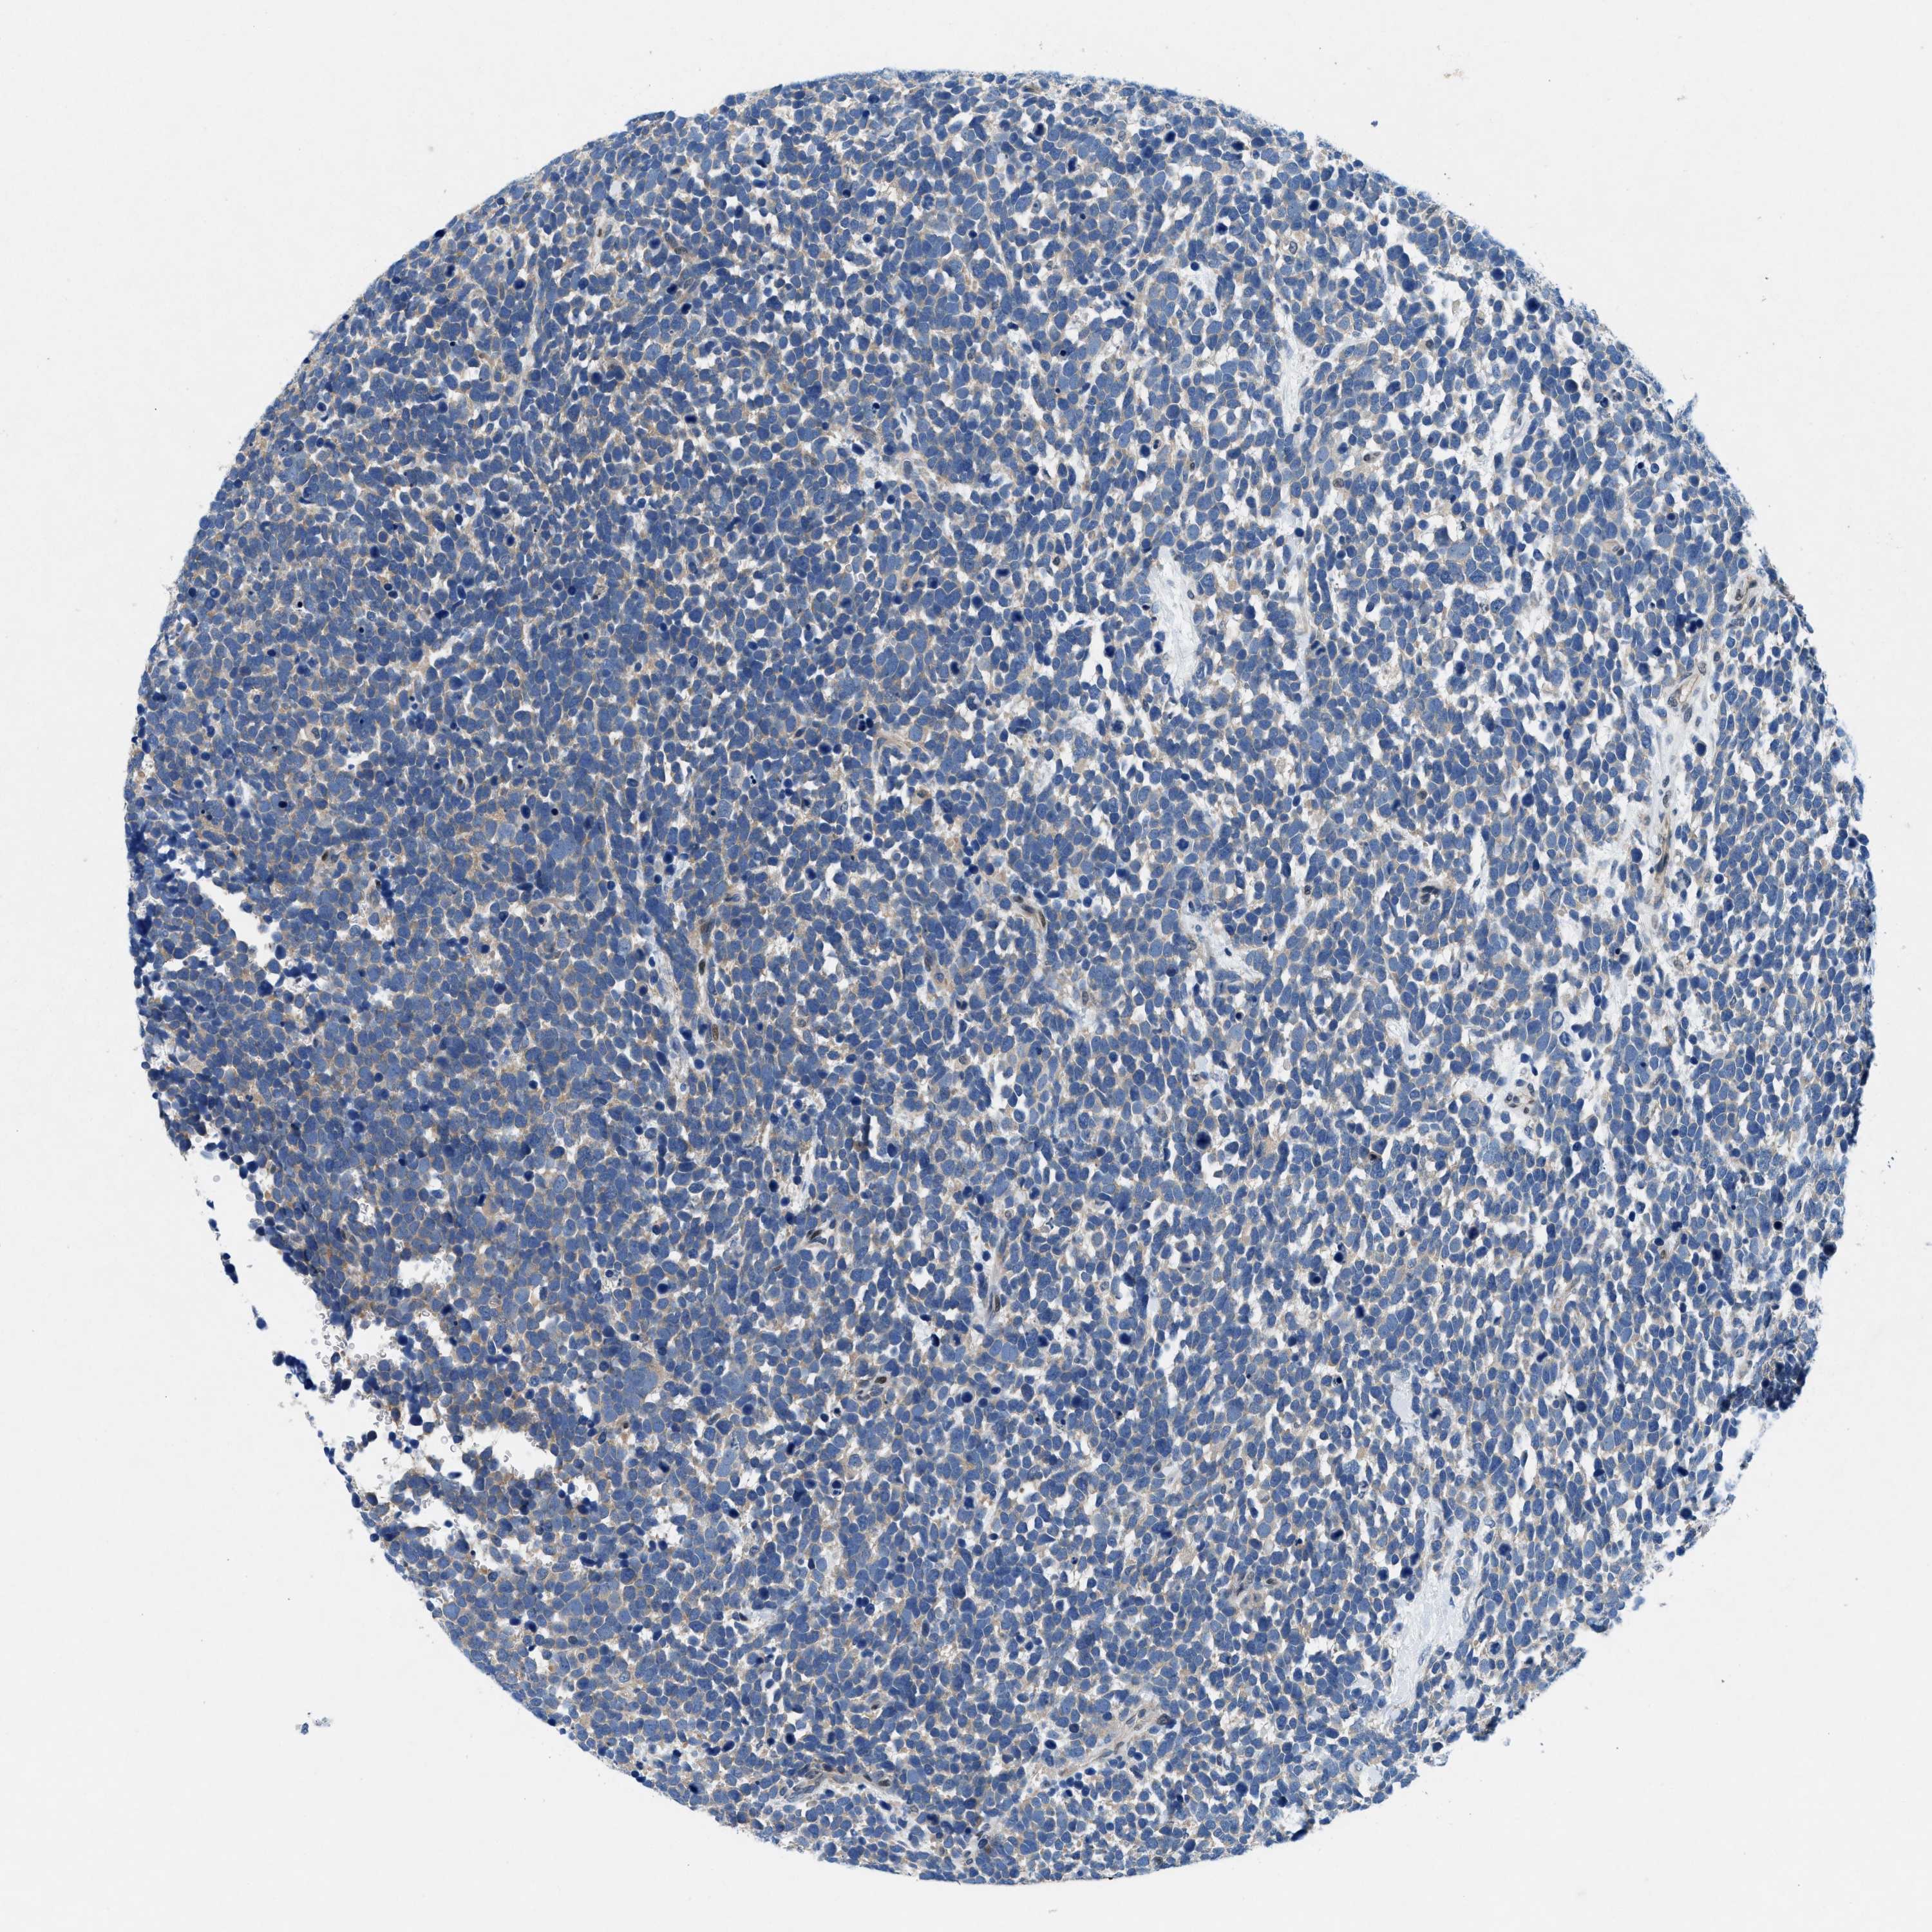

UROTHELIAL CANCER - Protein expressioni

A mouse-over function shows sample information and annotation data. Click on an image to view it in a full screen mode. Samples can be filtered based on level of antibody staining by selecting one or several of the following categories: high, medium, low and not detected. The assay and annotation is described here.

Note that samples used for immunohistochemistry by the Human Protein Atlas do not correspond to samples in the TCGA dataset.

Antibody stainingi

Antibody staining in the annotated cell types in the current human tissue is reported as not detected, low, medium, or high, based on conventional immunohistochemistry profiling in selected tissues. This score is based on the combination of the staining intensity and fraction of stained cells.

Each image is clickable and will lead to virtual microscopy that enables deeper exploration of all samples and also displays staining intensity scores, fraction scores and subcellular localization as well as patient and tissue information for each sample.

Antibody HPA016867

Antibody HPA018271

Urothelial carcinoma, Low grade

Urothelial carcinoma, High grade